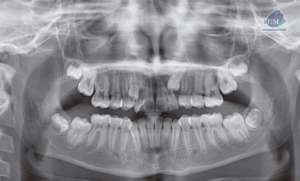

Paciente masculino de 09 años de edad acude al Instituto de Diagnóstico Maxilofacial para una tomografía de campo mediano (10 x 10mm) con el motivo